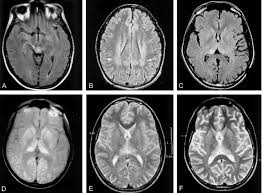

Image: American Journal Of Neuroradiology

Researchers analyzed autopsies of British patients ages 36 to 51. The patients are thought to have developed Creutzfeldt-Jakob disease (CJD) through treatment with human growth hormone from cadavers. CJD is a rapidly progressing degenerative brain disease that is similar to Alzheimer’s.

In addition to CJD, the report showed another abnormality. Six patients showed precursors for beta amyloid proteins, which may have been caused by genetic mutations associated with early-onset Alzheimer’s.

Amyloid plaques are the main proteins found in the brains of Alzheimer patients. The presence of these proteins caused the researchers to question if the human growth hormone procedures could somehow transmit the building blocks for degenerative brain disease.